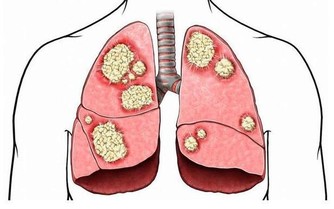

近一個月前,年僅27歲韓國男藝人金宇彬宣布患鼻咽癌,引起一片嘩然。

最近,金宇彬所在的公司透露了他的治療近況:

因擔心手術可能造成腦部的後遺症,金宇彬選擇接受放射治療。

大家都知道,放射治療是一種通過對局部進行照射放射線的治療方法,是治療癌症的最常用的手段之一。

大家可能不知道的是,鼻咽癌的放射治療的常見後遺症包括:

張口困難、聽力功能障礙、頸部纖維硬化、中樞神經系統損傷等,且後遺症出現的機率均在10%左右。

即使如此,金宇彬依然要選擇放射治療,說明手術以及手術後遺症所帶來的的風險遠遠大於放射治療帶來的風險。